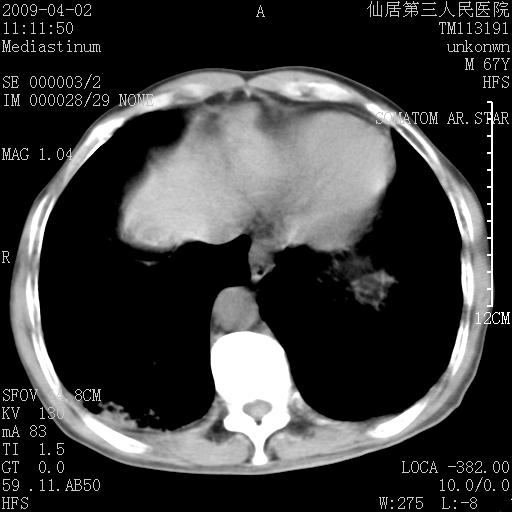

患者老年男性,乏力畏寒来诊,摄胸片示右下肺感染性病变,抗炎两周后复查胸片,无好转有进展。

后做ct平扫表现如下:

病灶呈蜂窝征,纵隔多个淋巴结肿大;肺泡癌需考虑

右肺下叶背段干酪性肺炎。请痰检[emb28]

考虑双肺间质性改变(间质纤维化?)伴右肺下叶感染。

考虑间质性肺炎可能性大,患者卧床吗?坠积性肺炎代排

支持11楼,考虑肺结核.年䶨;大,抗炎无效.纵隔淋巴结肿大.老年人下肺结核要警提